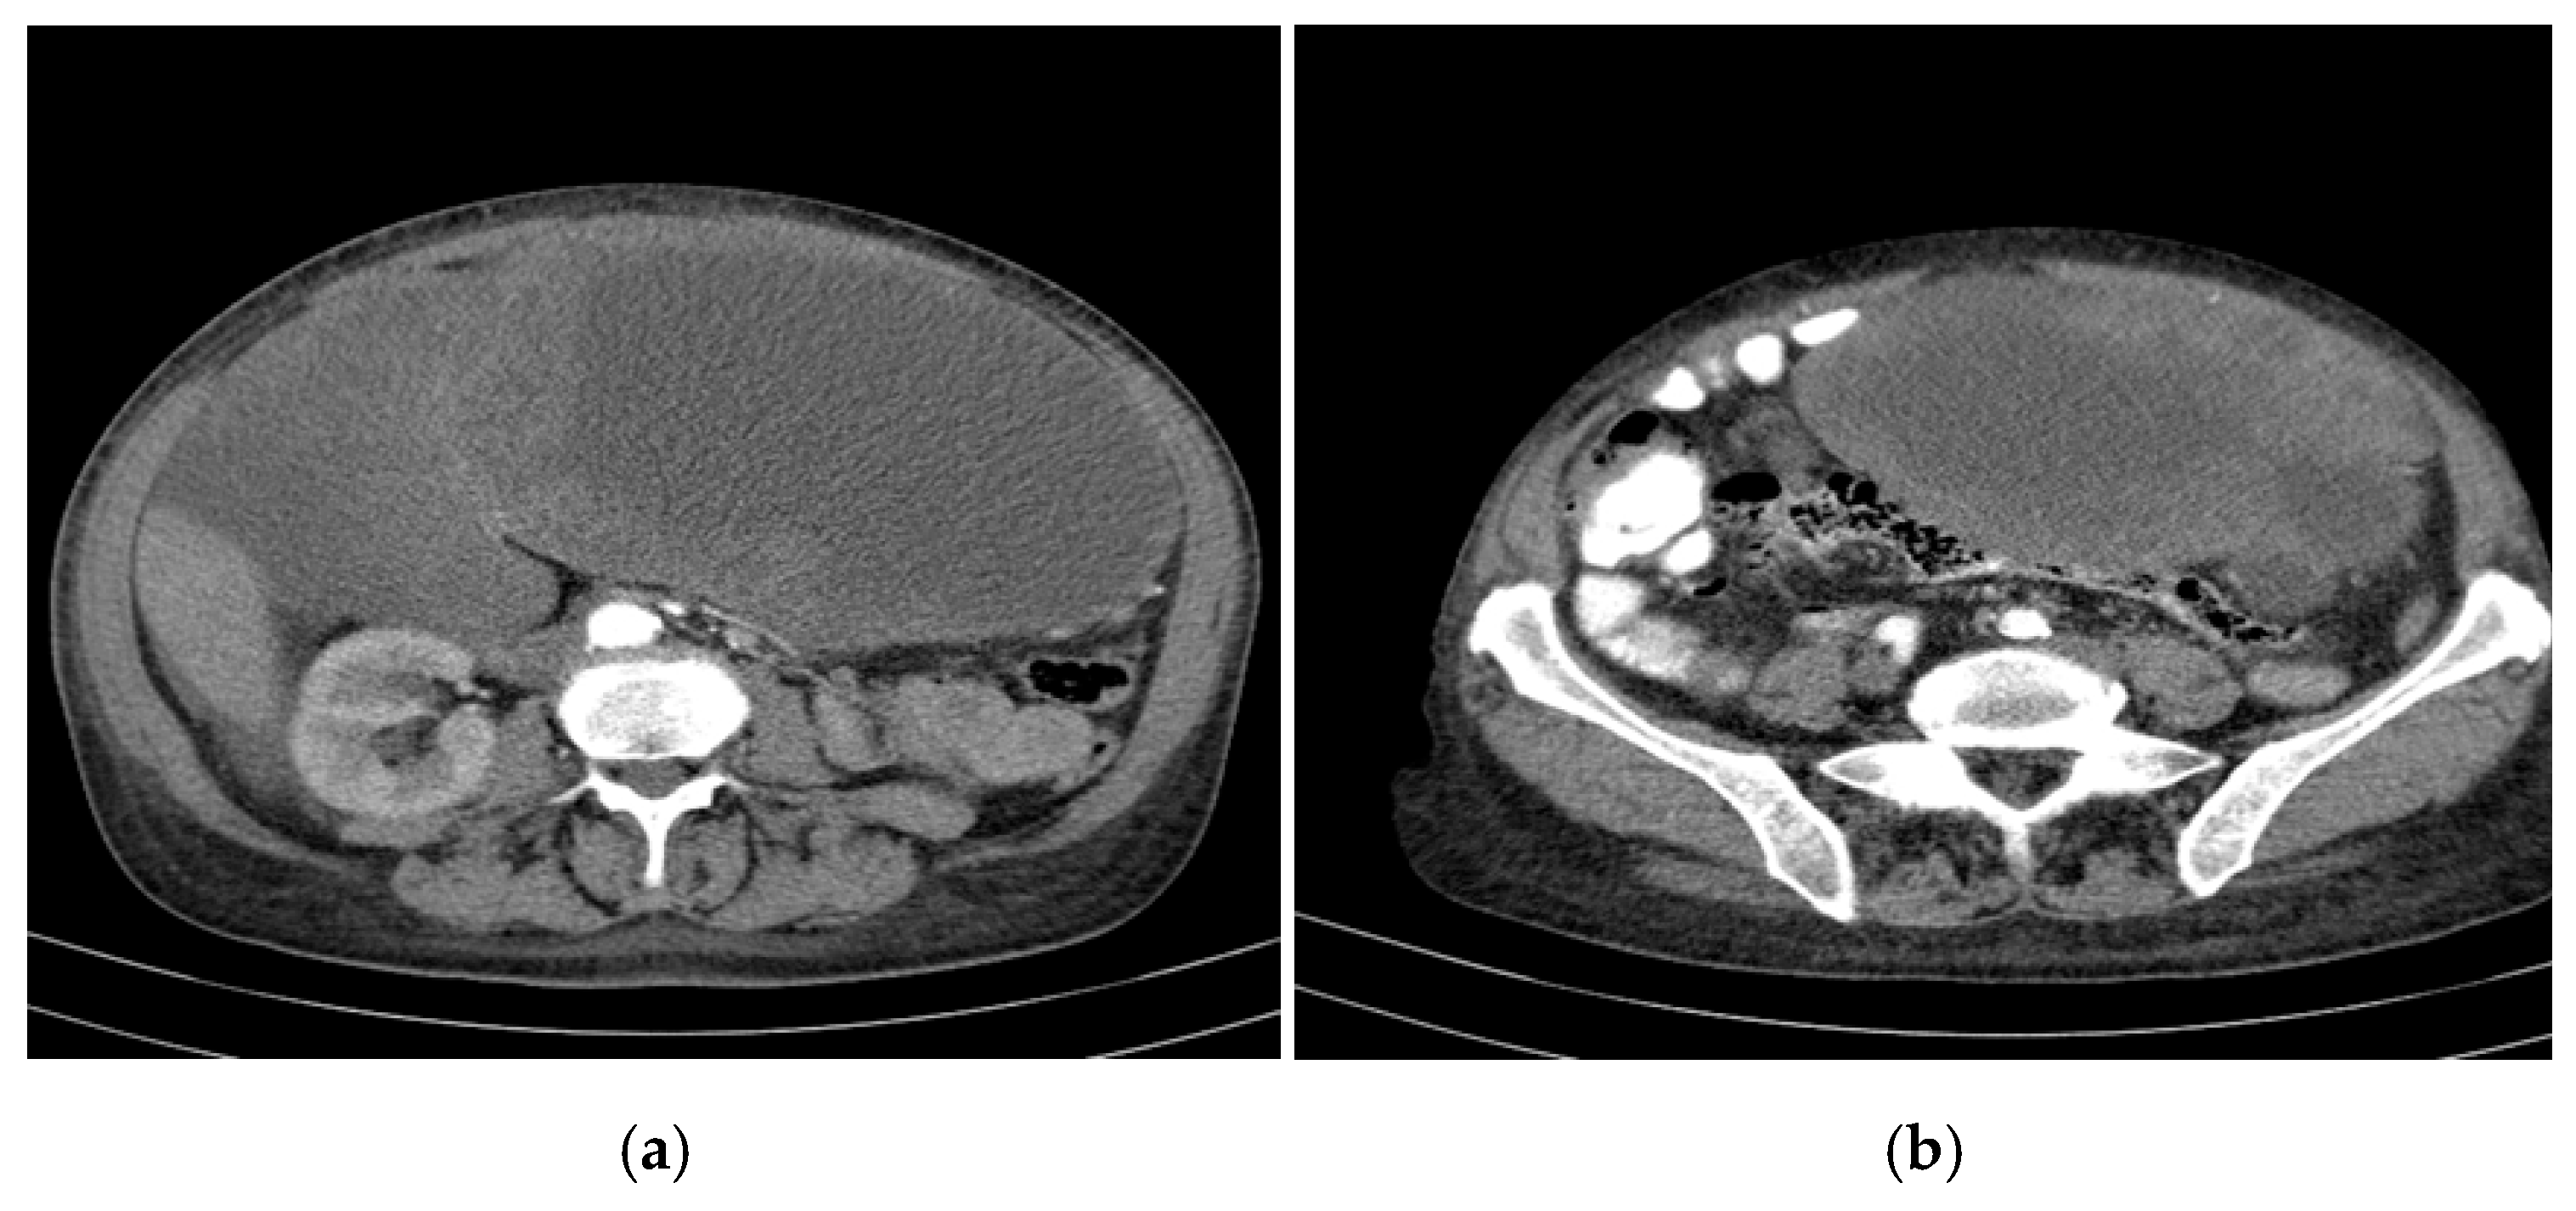

- Regression of extrahepatic lesions: Initial gastric and peritoneal lesions, including a cystic formation in the anterior gastric wall and ascitic fluid, regressed significantly by month 14 and did not reappear in later scans. The left inguinal hernia, although noted consistently, remained unchanged, without complications.

- Emergence of new findings without aggressive progression: A subcapsular nodule (3.5 × 2 cm) in Morrison’s space was identified during month 41, remaining stable without concerning enhancement patterns. A pseudo-nodular perfusion anomaly in segment VIII was noted but was attributed to pressure from the large cystic tumour rather than neoplastic progression. Mild gastric antral wall thickening developed later (by month 49), with a maximum thickness of 14 mm, but remained stable thereafter, with no associated adenopathy or signs of malignant transformation.

- Absence of significant distant metastases or new systemic involvement: Throughout the entire monitoring period, there were no newly detected secondary metastatic lesions in the thoracic, abdominal, or pelvic regions; no significant adenopathy was identified; and there was no recurrence of ascitic fluid beyond a mild amount in the early monitoring phases.

- Imaging: Abdominopelvic CT showed numerous cystic liver lesions (1 cm to 18 cm), mostly in the right hepatic lobe. Largest cysts in segments IVb and III of the left hepatic lobe.